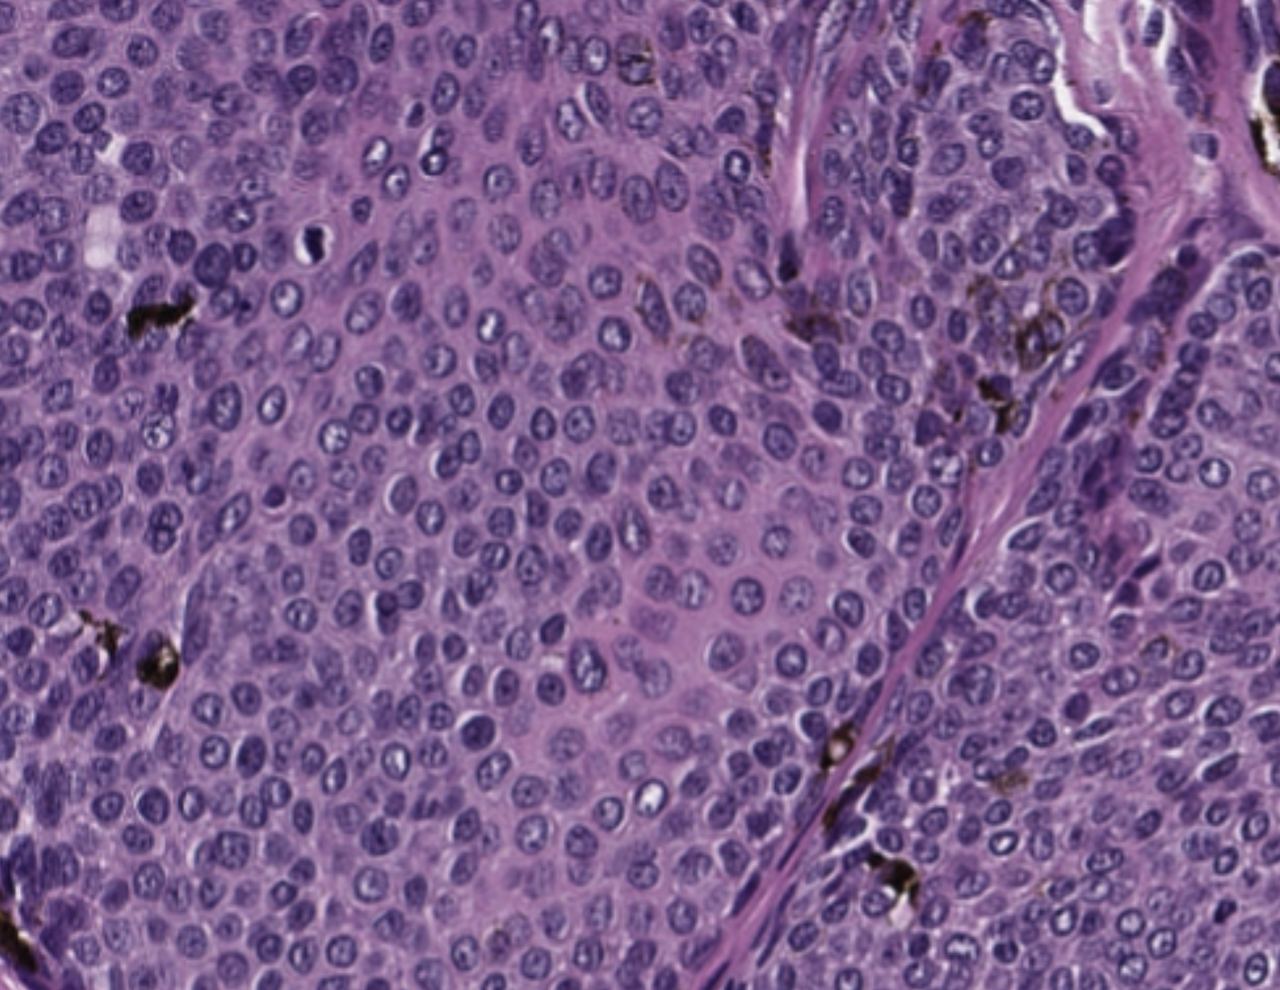

Базально - клеточная опухоль